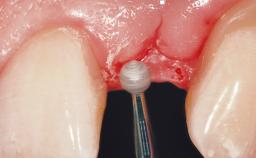

Immediate Flapless Placement of an Implant in a Maxillary Left Central Incisor Site

A 29-year-old female patient presented for treatment to replace the upper left central incisor tooth with an implant- supported restoration. The tooth had been intermittently symptomatic for the previous 12 months. The tooth had originally suffered trauma about 15 years previously. Several endodontic treatments had been performed, including an apicectomy procedure to retain the tooth. The patient was healthy and a non-smoker. She had reasonable expectations in regard to esthetic outcomes and the risk of marginal tissue recession following treatment. At medium smile, the gingival margins of the upper teeth were visible, with a display of 3 to 4 mm of the gingival margins. Gingival recession of tooth 21 and a discrepancy in the gingival levels between teeth 11 and 21 was observable during normal speech and smile.

Soft Tissue Contour and Volume Slightly compromised